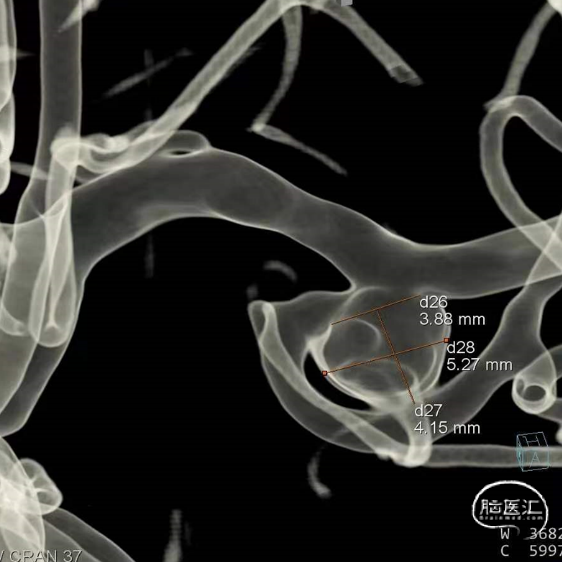

经测量可得动脉瘤宽度平均值为7.28mm,动脉瘤最小高度为4.91mm,参考尺寸选择表,选择WEB™ SL 8*4。

经测量可得动脉瘤宽度平均值为7.0mm,动脉瘤高度为5.18mm,选用WEB™ SL 8*4。

经测量可得动脉瘤宽度平均值为8.88mm,动脉瘤最小高度为7.71mm,瘤颈约为4.03mm。参考尺寸选择表,选择WEB™ SL 10*5,VIA™ 33微导管。

动脉瘤平均宽度5.41mm, 最小高度为3.71mm,瘤颈约为4.94mm,使用WEB™ SL 6*3mm瘤内扰流装置进行栓塞治疗。

经测量可得动脉瘤宽度平均值为7.0mm,动脉瘤高度为7.4mm,最终选择WEB™ SL 9*6。

经测量可得动脉瘤宽度平均值为9.1mm,动脉瘤最小高度为8.9mm,最终选择WEB™ SL 11*6。